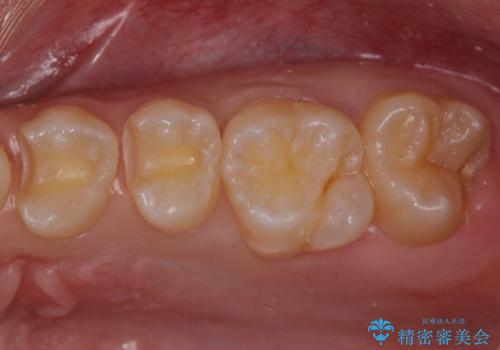

歯と歯の間の虫歯 セラミックインレーでの治療

- 検査の結果、歯と歯の間に大きな虫歯が確認されました。

セラミックでの治療をご希望されたため、セラミックインレーでの治療を行いました。

- 左上45 セラミックインレー 7,7000円×2本 費用は治療当時の料金となります

今回は残せる歯の厚みが十分確保できたため、インレーでの修復処置となりました。